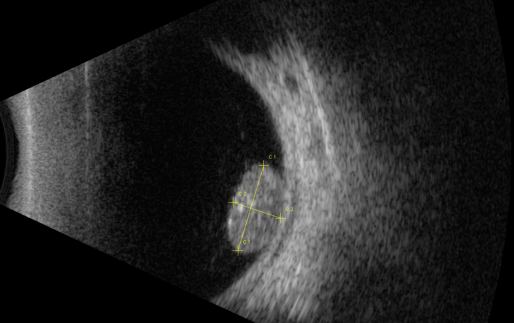

視網(wǎng)膜母細(xì)胞瘤的分類(lèi)和治療

視網(wǎng)膜母細(xì)胞瘤是嬰幼兒常見(jiàn)的眼內(nèi)惡性腫瘤,可危害患者的視力、眼球和生命。其惡性程度高,多發(fā)于兒童,尤其是3歲以下的兒童,常表現(xiàn)為白瞳癥,可侵及單眼或雙眼。

根據(jù)腫瘤的表現(xiàn)和發(fā)展過(guò)程可分為眼內(nèi)期、青光眼期、眼外期和全身轉(zhuǎn)移期。

開(kāi)始在眼內(nèi)生長(zhǎng)時(shí)外眼正常,因患兒年齡小,不能自述有無(wú)視力障礙,因此本病早期一般不易被家長(zhǎng)發(fā)現(xiàn)。當(dāng)腫瘤增殖突入玻璃體或接近晶體時(shí),瞳孔區(qū)出現(xiàn)黃白色反光,如貓眼樣(“黑貓眼”),此時(shí)常因視力障礙而瞳孔散大、白瞳癥或斜視被家長(zhǎng)發(fā)現(xiàn)。